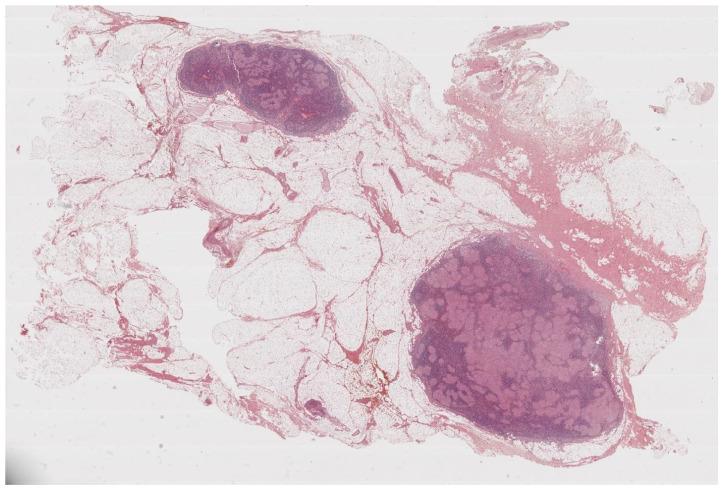

Sarcoidosis is a chameleon disease of unknown etiology, characterized by the growth of non-necrotizing and non-caseating granulomas and manifesting with clinical pictures that vary on the basis of the organs that are mainly affected. Lungs and intrathoracic lymph nodes are the sites that are most often involved, but virtually no organ is spared from this disease. Histopathology is distinctive but not pathognomonic, since the findings can be found also in other granulomatous disorders. The knowledge of these findings is important because it could be helpful to differentiate sarcoidosis from the other granulomatous-related diseases. This review aims at illustrating the main clinical and histopathological findings that could help clinicians in their routine clinical practice.